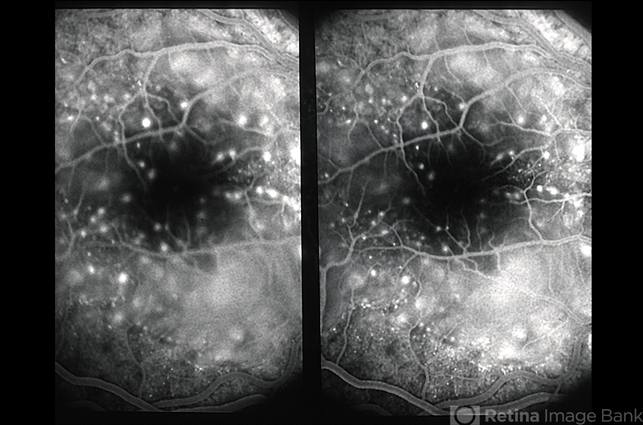

- hypofluorescent spots, stereo pair

- FA, multiple punctate hyperfluorescent dots stereo.